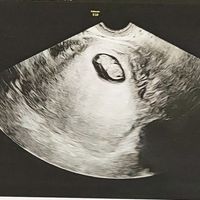

Hola! Me he animado a abrir el post y espero que poco a poco seamos muchas 🤰🏼. Yo vi mi positivo el pasado sábado y mi FPP es el 11 de Mayo. Todavía estoy de muy poquito y al ser primeriza total me...